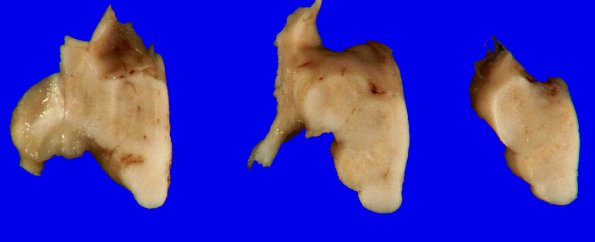

The medulla was shrunken and the ION atrophic resulting in changes in the typical contours of the medulla.